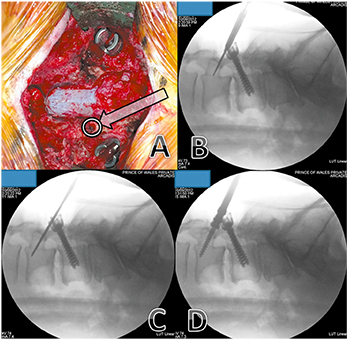

Fig. 1 L3–4 instrumented posterolateral fusion—previous L4-S1 onlay fusion performed 12 years ago. (A) The starting point (arrow) is at the pars

interarticularis, inferior to the mobile cranial facet joint. (B) Image intensifier image showing it use for directing the drill in the planned trajectory.

(C) Image intensifier image showing that, because most of the of bone traversed in this technique is cortical bone, the hole is tapped up to the

planned screw diameter. (D) Image intensifier image showing insertion of screw.

- See Figures 1A, 2. The initial starting point is medial on

the pars. The surgeon needs to remove the inferior 1⁄2 of

the spinous process to achieve the appropriate angulation

for the trajectory. A lateral II image (Fig. 1B) should be

taken to confirm the correct angulation. We prefer to

perform this step with a 2 mm high speed round burr drill

and not a pedicle probe due to risk of fracture of the pars.